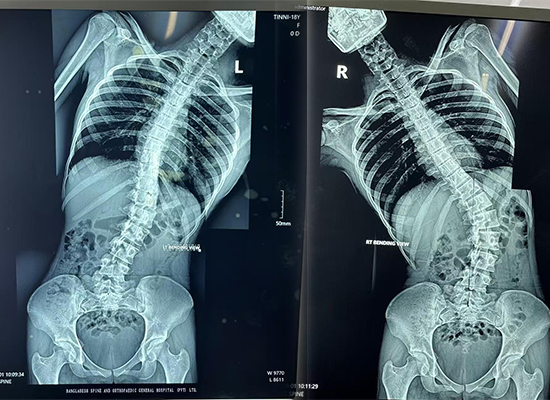

Предоперационная визуализация показала:

Выраженное латеральное искривление грудопоясничного отдела позвоночника.

Ротация позвонков и выступание ребер

Несбалансированные плечи и положение туловища

Эти данные подтвердили необходимость коррекции задней деформации позвоночника и спондилодеза с использованием конструкции транспедикулярный винт-стержень..

Предоперационная рентгенограмма всего позвоночника, показывающая грудопоясничный сколиоз у 16-летнего пациента из Дакки, Бангладеш.